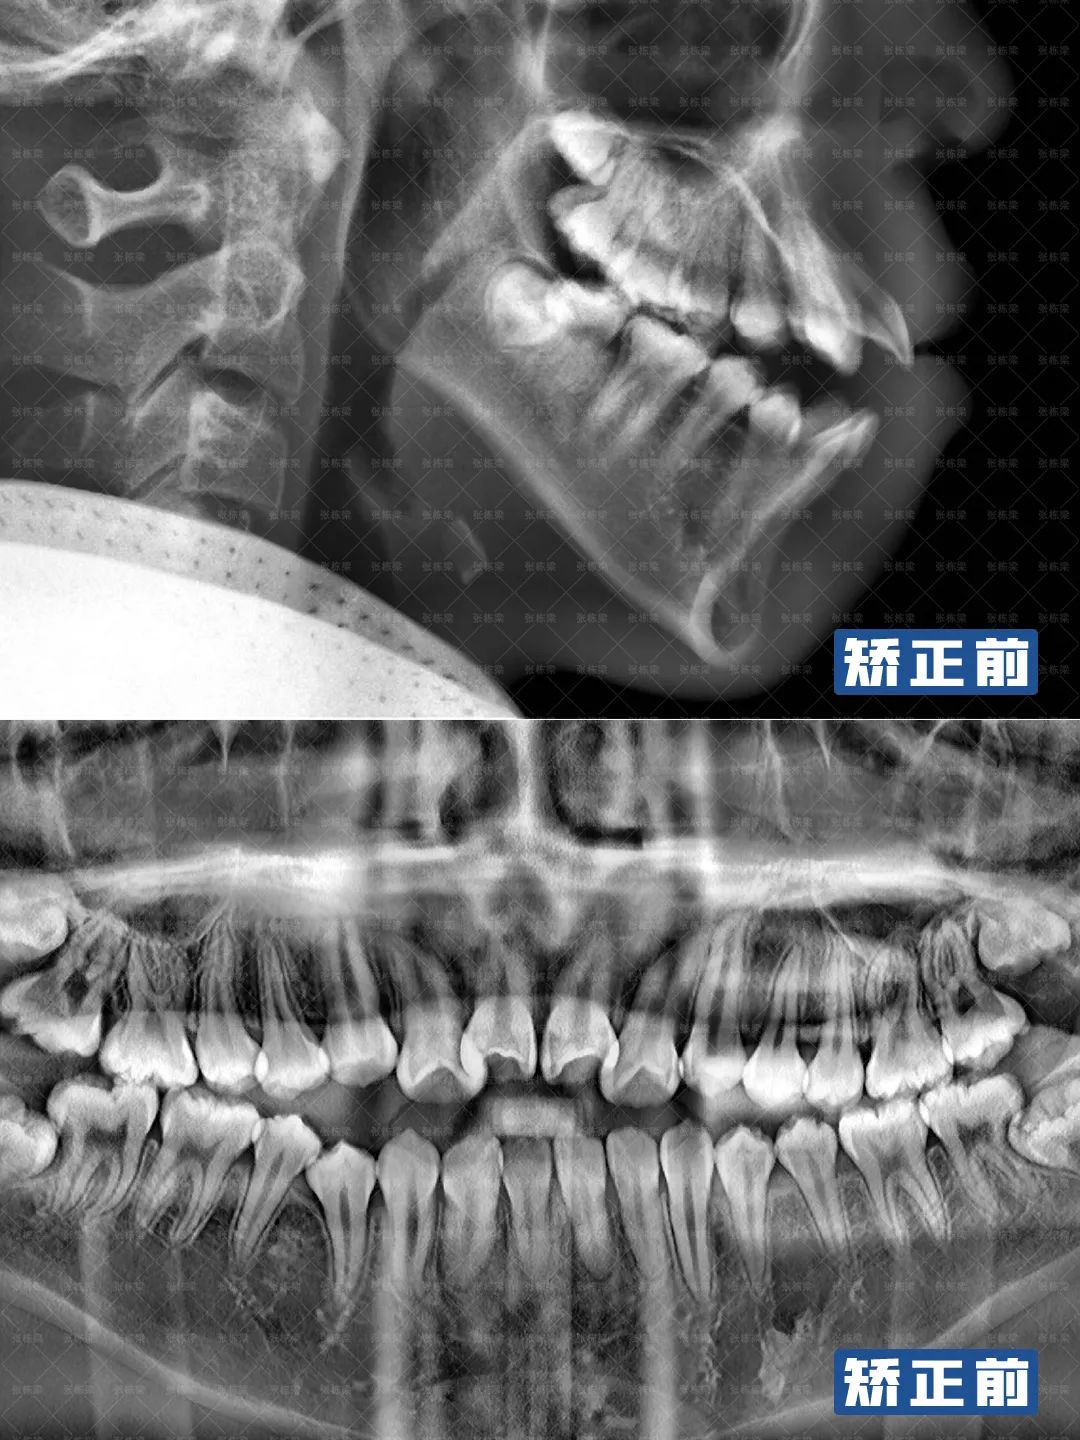

综合牙片面型分析:

1、头侧片、全景片可见:牙根,牙槽骨无异常,关节无异常,有智齿,前牙唇倾,下颌颌平面倾斜,上颌补偿曲线较深,双颌前凸,颏部后缩,前牙开颌;

2、正面观:面部双侧基本对称,颏点正中,面下1/3高度稍长,无露龈笑,放松时开唇露齿,闭嘴时颏肌紧张;

4、口内检查:口腔卫生良好;双侧磨牙近中关系;前牙重度开颌;

5、牙列:恒牙列,上前牙唇倾,上牙弓尖圆形,牙弓狭窄,lll度拥挤。下牙弓方圆形,l度拥挤,双侧下颌后牙近中倾斜;